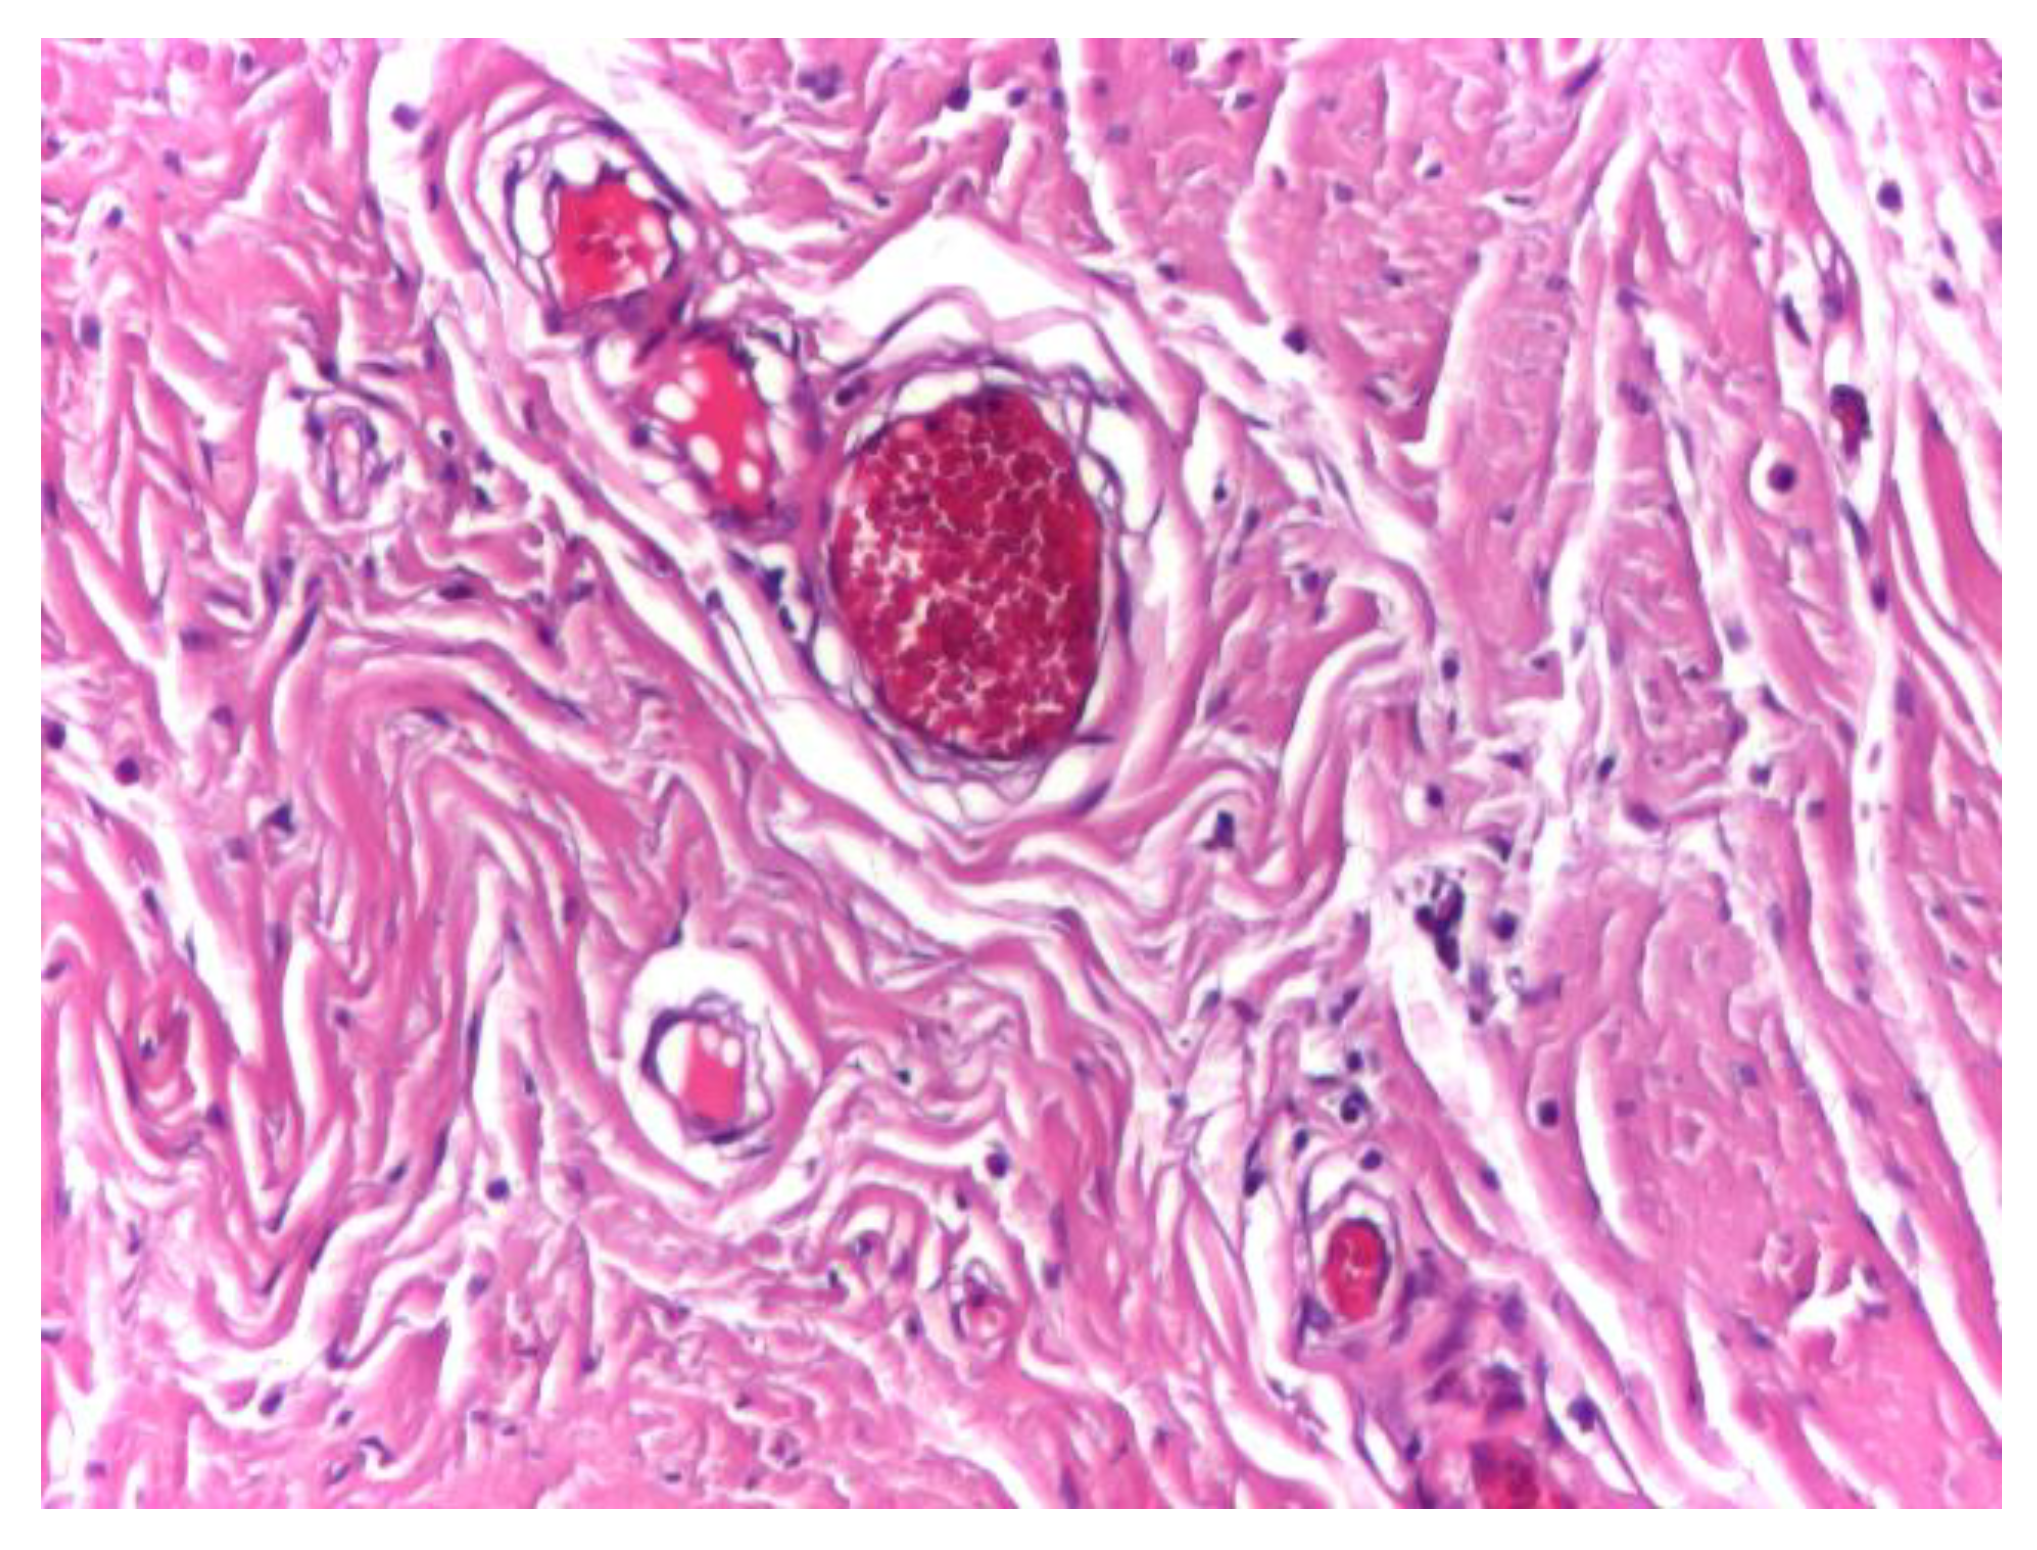

Vascular structures were infrequently observed within the aponeurotic tissue and displayed preserved wall integrity, with discrete intraluminal stasis. No perivascular inflammatory infiltrate, endothelial damage, or pathological vascular remodeling was identified in the surrounding connective tissue (Figure 3).

Figure 3. Optical microscopy of human aponeurotic tissue showing vascular structures with preserved wall integrity and discrete intraluminal stasis, without associated inflammatory reaction. Hematoxylin and eosin staining (H&E); original magnification ×10.